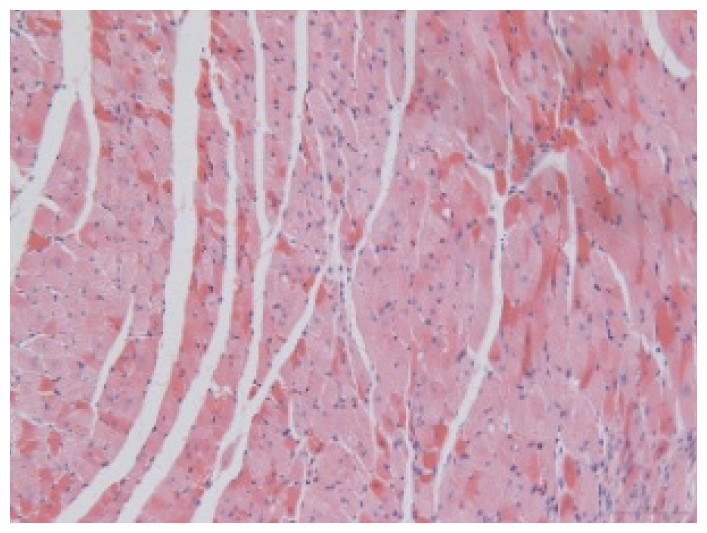

2.1.7. CoPP Treatment Inhibited Ventricular Remodeling of Post-Infarction in SHR

| Groups | Masson (macroscopic) | Masson (×200) | Infarct area (HE ×200) | Peri-infarct area (HE ×200) |

|---|---|---|---|---|

| WN | ![]() | ![]() | ![]() | |

| SMN | ![]() | ![]() | ![]() | ![]() |

| SMC | ![]() | ![]() | ![]() | ![]() |

| SMS | ![]() | ![]() | ![]() | ![]() |